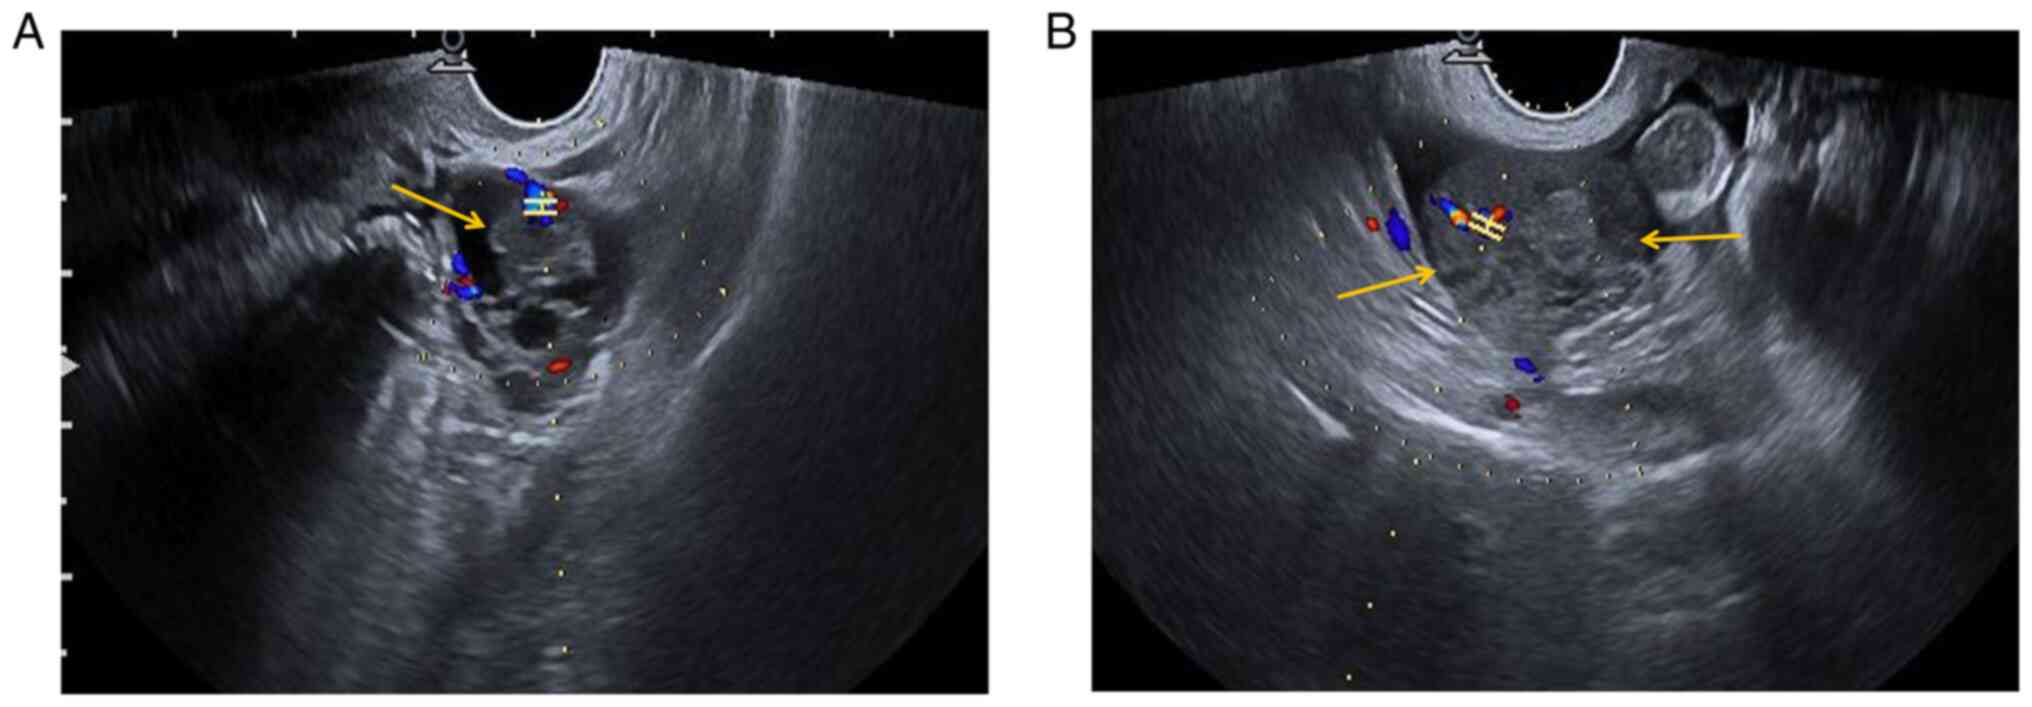

Preoperative ultrasonography (US) examination revealed a mixed cystic-solid sonographic appearance of 37x26x35 mm in the left adnexal area and the solid area was 17x14x22 mm (yellow arrow). In the left adnexal area, CDFI indicated the following: RI, 0.68; PSV, 12.9 cm/sec; and EDV, 4.1 cm/sec (Fig. 1A). In the right adnexal area, a low-echo area of 54x26x41 mm with an irregular shape (yellow arrows) was present and CDFI indicated the following: RI, 0.48; PSV, 22.9 cm/sec; and EDV, 11.8 cm/sec (Fig. 1B). A certain amount of pelvic fluid collection and a small amount of effusion in the uterine cavity were detected.

Figure 1

Preoperative US findings. (A) Preoperative US examination indicated a mixed cystic-solid area of 37x26x35 mm in the left adnexal region, and the solid area was ~17x14x22 mm (yellow arrow). CDFI of the left adnexal area indicated the following: RI, 0.68; PSV, 12.9 cm/sec; and EDV4.1 cm/sec. (B) A low echo area of 54x26x41 mm with an irregular shape was observed in the right adnexal area (yellow arrows). CDFI indicated the following: RI, 0.48; PSV, 22.9 cm/sec; and EDV, 11.8 cm/sec. H-shaped structure indicates the sample gate. The color represents the direction of blood flow. Red indicates blood flow towards the probe and blue means blood flow away from the probe. A certain amount of pelvic fluid collection and a small amount of effusion in the uterine cavity were observed. US, ultrasonography; RI, resistive index; PSV, peak systolic velocity; EDV, end-diastolic velocity; CDFI, color Doppler flow imaging.